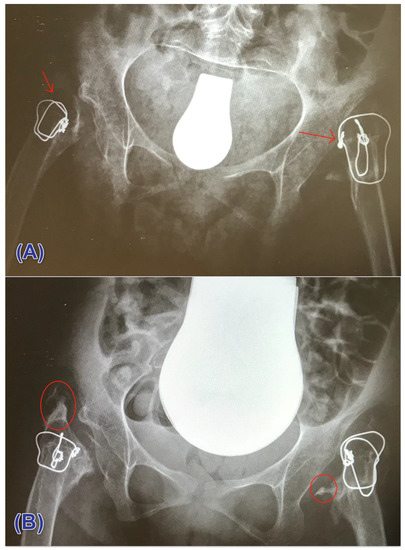

3.3. Heterotopic Ossification